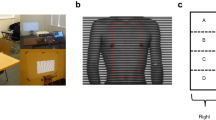

For this prospective study, all patients with pectus excavatum between 6 and 30 years of age, who presented for chest wall deformities in the Department of Pediatric Surgery between January 2020 and June 2021, were included. Real-time MRI of the thorax was performed to determine the thoracic dimensions and indices HI, CI, AI, and EI. Exclusion criteria included contraindications to MRI, such as claustrophobia and carrying metallic or electronic implants incompatible with MRI. Patients with a sterno-vertebral distance of less than 5 mm were excluded, assuming that the limited spatial resolution would have a considerable impact on index measurement (Fig. 1). The study was approved by the Institutional Review Board (169–20ek), and written consent was obtained from all subjects or their legal guardians.

For quiet and forced breathing conditions, the dimensions required for calculating the thoracic indices HI, CI, AI, and EI were determined from transverse images at the deepest point of the funnel (Fig. 1). This task was performed by a pediatric radiologist (D.G., 12 years of experience in pediatric MRI) with use of a conventional DICOM Viewer (syngo.plaza, Siemens). For assessment of interobserver variability, the analysis was independently performed by a study nurse (I.K., 8 h of training). Values of HI > 3.25 and CI > 28% were presumed as pathological according to the literature [14]. A correlation analysis between HI and CI was performed. Modified AI and EI measures (Fig. 1) were introduced to account for different lateralities, with 1 being subtracted from the ratio of larger diameter and smaller diameter. Right laterality was tagged with a negative sign.

Three distinct movement patterns characterized by selected frames of MRI videos and corresponding tracking curves in our cohort of patients with funnel chest. Please take note of the deactivated vacuum bell placed upon the funnel as part of our standard estimate of treatment response using real-time MRI. (Video 5a, Fig. 5b) Symmetric movement of both sides and funnel (Video 5c, Fig. 5d) pronounced movement of the lower side in asymmetric pectus excavatum, and (Video 5e, Fig. 5f) delayed movement of one side of the funnel